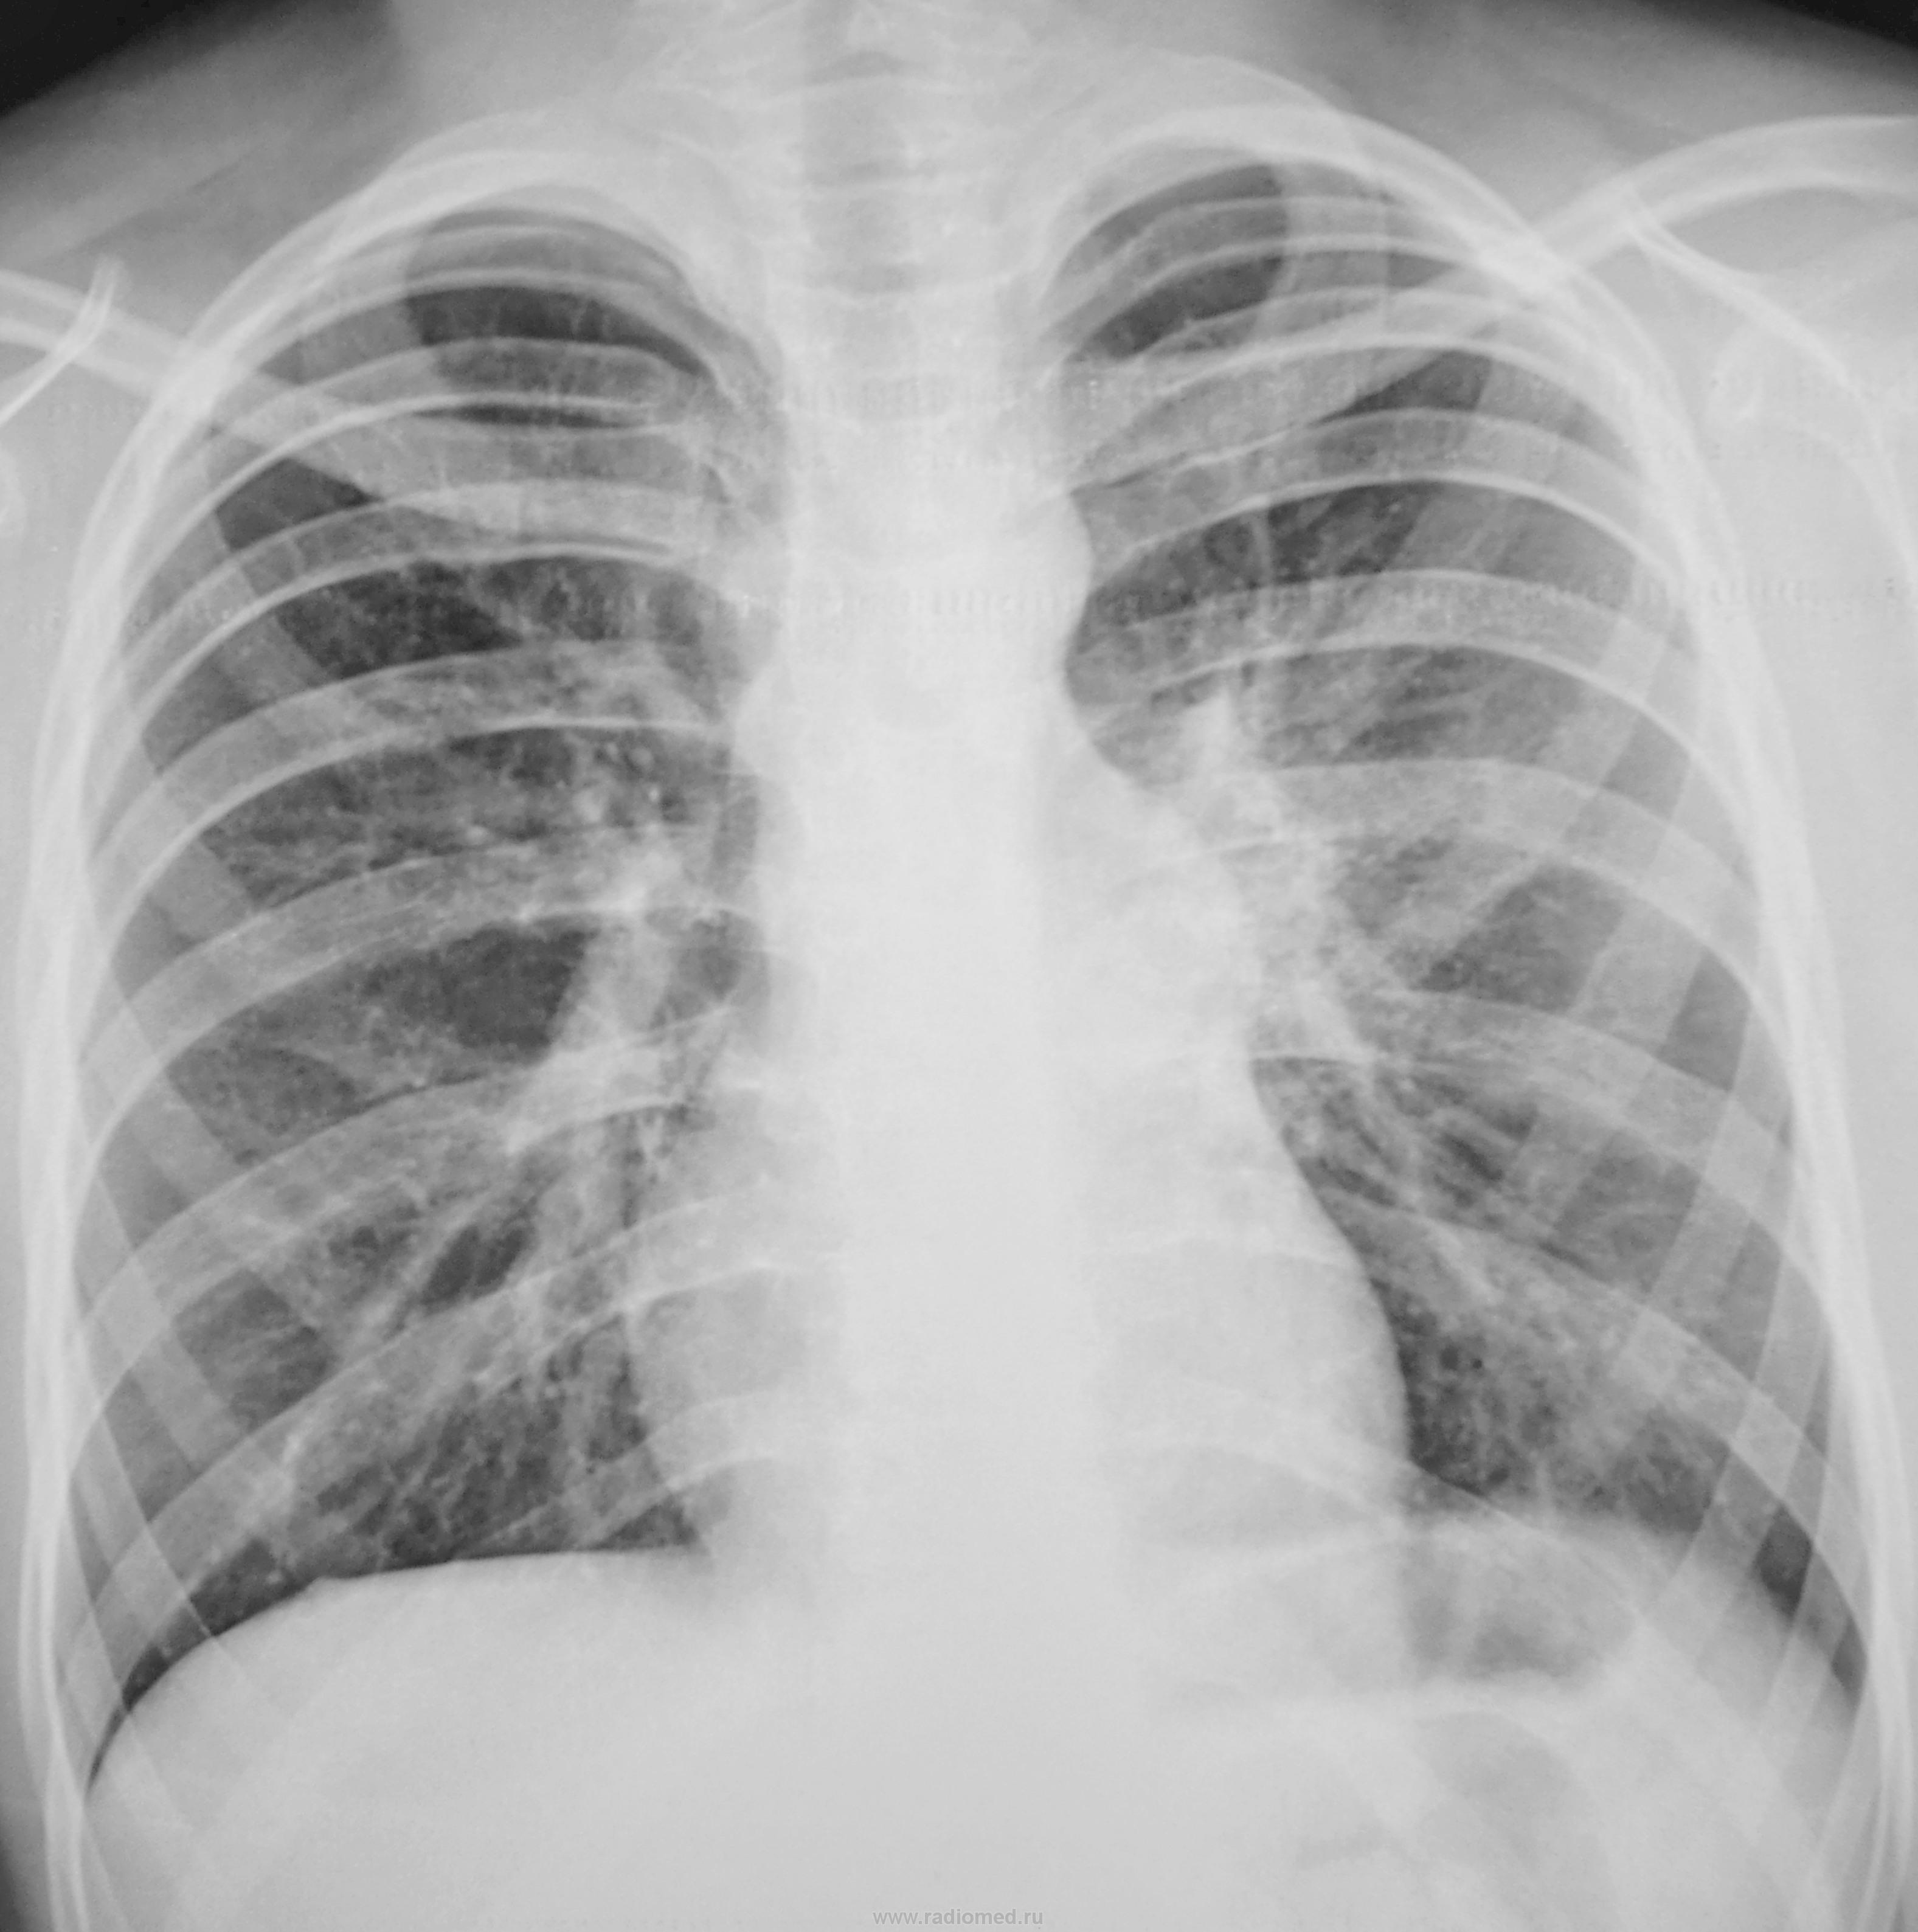

Подросток направлен на рентгенографию ОГК с диагнозом пневмония.

на фоне усиление л/рисунка очаговоподобные тени в верхних отделах.левый корень смушает.

Расширение контура легочной артерии, увеличение левого корня. Да и легочный рисунок усилен с обеих сторон, артерии как бы утолщены. Боковую проекцию в студию

Вполне может здесь оказаться пневмония S6 левого лёгкого. хотя по одной проекции сложно решить. Нужна боковая проекция. Вообще-то смущает корень левого лёгкого. Наверное, томограммы уже заготовлены).

PS. Ещё ствол лёгочной артерии сильно выбухает.

Инфильтрации в л/полях не вижу. Сосудистый рисунок акцентирован. Выбухает артериальный конус, индекс Мура 36% - признаки перегрузки правого желудочка (ВПС? - консультация кардиолога). Левый боковой рекомендовала бы только при наличии признаков воспаления по лабораторным данным.

Видимых очаговых и инфильтративных изменений в лёгких не выявлено. Митральная конфигурация сердца.

Рекомендовано: УЗИ сердца.